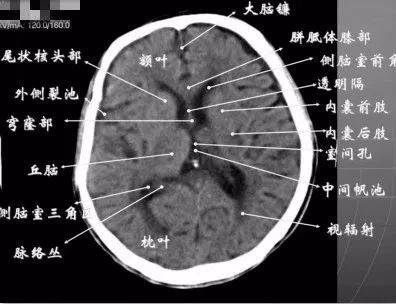

ct入门颅脑ct精美解剖详细标注

详细颅脑ct正常解剖图谱,带标注,值得收藏!

收藏超详细的头部ct读片详解